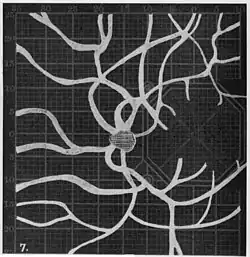

Angioscotomas were first discovered and mapped out by John Norris Evans (1891-02-28--1953-04-08)[2] in 1926, who coined the term angioscotometry to describe the painstaking charting of the scotoma of the retinal blood vessels by manual perimetry. He seated each subject in a seat in a dark setting, and tested whether they could see a tiny bright test object placed at various locations.[3] Using a 1.5 mm white disk, Evans reported intricate branch‑like scotomas that mirrored the arteries and veins emerging from the optic disc, with a full map requiring up to 2 hours to complete. He plotted this for subjects under various conditions, such as while holding breath, with glaucoma, etc. A year later, he confirmed that only short stump‑like scotomas had been noticed previously, some further data plotted with a smaller 1 mm stimuli, and under varying conditions on the subject.[4] He published a monograph on this in 1938 in which he described its use in assisting diagnosis of various conditions, such as retinal edema, glaucoma, optic neuritis, etc.[5]

In the 1940s there were further developments. Evans reviewed the state of research in 1942.[6] In 1945, Welt designed a portable campimeter and linked the size of both the blind spot and the angioscotoma to retinal arterial pressure.[7] In the same year, Weekers and Humblet published detailed tracings that overlaid vessel photographs onto Bjerrum screen plots, firmly establishing the one‑to‑one correspondence between vascular anatomy and scotoma shape.[8]

1. Pressure on globe shows only stumps of large vessels. 2. Holding the breath causes similar effect; also 3. Holding the head low. 4. Pressure on opposite eye widens arteries and still more veins, 5. Pressure on the carotid produces no definite effect. 6. Looking thru red glass brings out finer vessels. -

Widening of angioscotoma under various conditions (holding head lower than trunk; holding the breath; making digital pressure on the same eye; (a vein) on opposite eye; (an artery) on opposite eye).